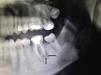

Varón de 32 años de edad, sin antecedentes médicos de interés, que acudió a consulta de dermatología por presentar un tumor en forma de cuerno cutáneo engastado en la piel, situado en la rama horizontal mandibular izquierda (fig. 1). En la exploración de la cavidad oral no se apreciaron alteraciones. Refería dolor a la palpación en esa zona. Había realizado tratamiento con pomada tópica de mupirocina 2% sin notar mejoría. Se realizó ecografía cutánea en modo B (Esaote®, Génova, Italia, sonda 18MHz) donde pudimos observar una estructura hipoecogénica en banda, algo tortuosa y medianamente delimitada que alcanza la superficie de la cortical ósea mandibular (fig. 2). El estudio mediante modo doppler mostró vascularización en la zona circundante a dicho trayecto, revelando signos inflamatorios que se complementaban con un contorno hipoecogénico mal definido en modo B (fig. 3). Con el diagnóstico de fístula dentocutánea el paciente fue derivado al servicio de cirugía maxilofacial, donde se completó el estudio con una ortopantomografía, detectándose una imagen radiolúcida apical que englobaba la raíz posterior del primer molar izquierdo (fig. 4). Se realizó tratamiento conservador mediante endodoncia y restauración, con una obturación de amalgama, curando la fístula cutánea en 20 días.

Recientemente Shobatake et al. han publicado 3 casos de fístulas dentocutáneas diagnosticadas por ecografía5. La ecografía dermatológica muestra un trayecto fistuloso hipoecogénico en banda, algo tortuoso y medianamente delimitado que alcanza la superficie de la cortical ósea con mayor o menor vascularización en el modo doppler, siendo un patrón sonográfico bien definido. Es una herramienta que complementa con rapidez otras técnicas radiológicas, y se presenta como una excelente opción para facilitar el diagnóstico de este tipo de lesiones, incluso en dermatólogos no especialmente diestros en el manejo de la enfermedad oral. Además, posibilita la monitorización terapéutica y la valoración de la probable inflamación asociada, para facilitar una posible profilaxis antibiótica previa a la intervención.